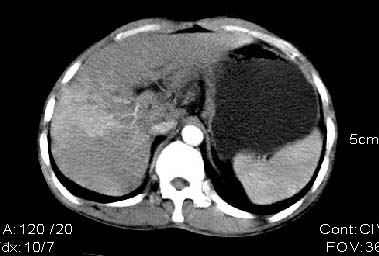

男:42岁。反复恶心呕吐半年。b超:右肝内多发占位,胆石胆囊炎.胆总管扩张

本例特点动脉期右叶近肝门区可见高密度强化,后段也见早期强化,静脉期肝门区高密度区造影剂退出,余密度均匀,考虑肝癌伴动静脉漏,肝右叶上段可见扩张胆管,考虑由于肿瘤压迫胆管引起阻塞,

鉴别 胆管细胞性肝癌,无动脉期强化,

首先我要谢谢战友给我的建议,明天我将给患者作平扫。以上为动静脉期的单幅图象资料。